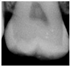

| 0 | Sound![]() | No shadow![]() | No radiolucency![]() |

| 1 Early | First Visual change in enamel![]() | Thin grey shadow into enamel![]() | Radiolucency in outer half of enamel![]() |

| 2 Distinct | Distinct Visual change in enamel ![]() | Wide grey shadow into enamel![]() | Radiolucency in inner half if enamel +/- Enamel dentin junction![]() |

| 3 Distinct | Localized enamel breakdown![]() | Shadow less than 2mm in dentine![]() | Radiolucency limited to outer 1/3 of dentine![]() |

| 4 Distinct | Underlying dentinal shadow![]() | Shadow more than 2 mm in dentine![]() | Radiolucency passed 1/3 of dentine![]() |